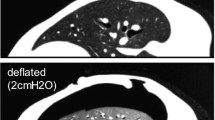

A pulmonary respiration model for deformable registration of lung CT for the surgery path planning and surgical navigation is an important, difficult, and time-consuming task. This paper presents a new fast deformable registration method for 4D lung CT in a hybrid framework incorporating point set registration with mutual information registration.

The point sets of the lung surface and vessels are automatically extracted. Their displacement vectors are obtained by point set registration. The sum of squared Euclidean distance between the displacement vectors of these point sets and the displacement vectors based on the B-spline transformation model is minimized as a novel similarity measure to derive the rough transformation function. Finally, the rough transformation function is refined by using the mutual information-based registration method. To evaluate the effectiveness of the proposed method, the authors performed registrations on 20 4D lung volume cases from two different CT scanners. The proposed method was compared with the point set-based method, the mutual information-based method, and the ANTS method, which is a state-of-the-art deformable registration technique.